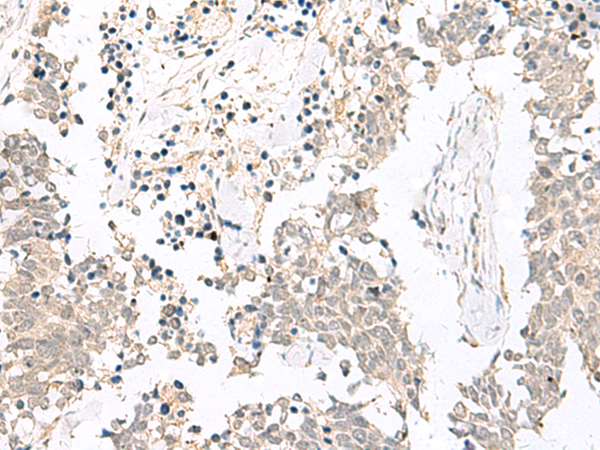

IHC positive control: |

Human lung cancer and Human esophagus cancer |